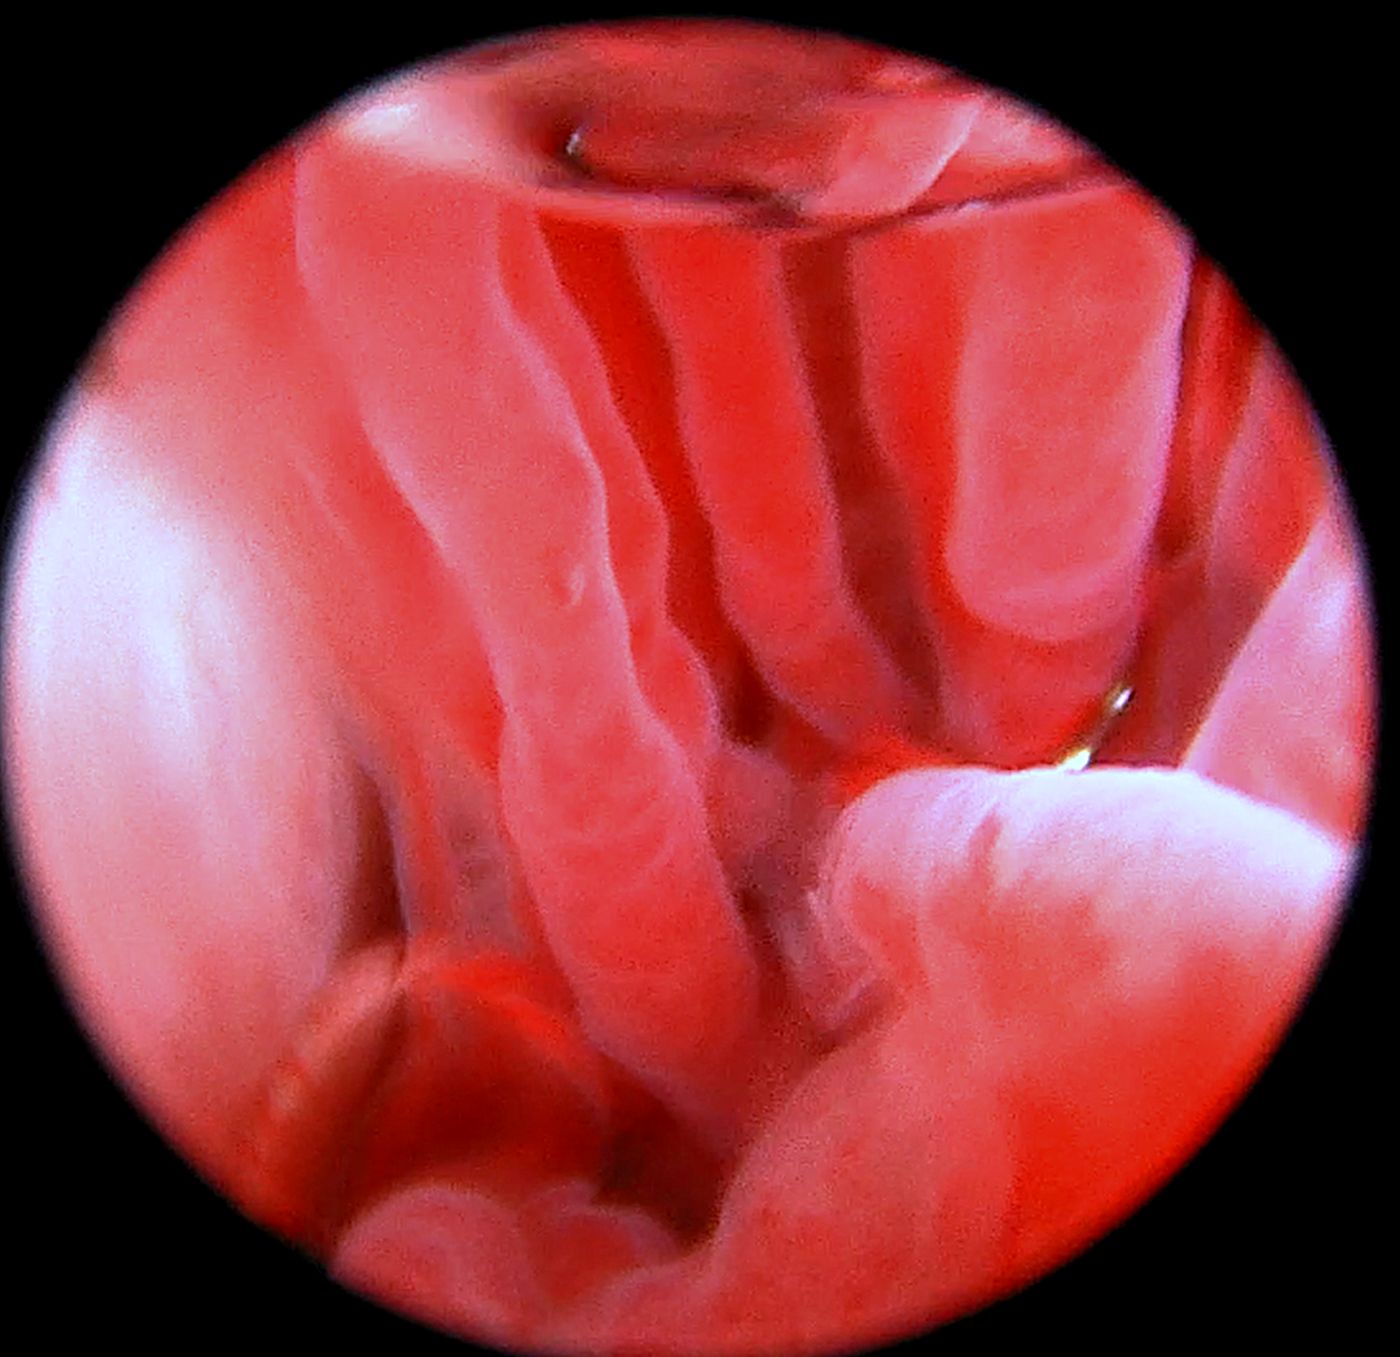

Diagnostyka endoskopowa układu oddechowego (laryngoskopia, tracheoskopia, bronchoskopia)

Zalecana w przypadku:

Przewlekłego lub napadowego kaszlu

Trudności w oddychaniu

Świszczącego lub chrapiącego oddechu

Objawów zespołu ras brachycefalicznych

Podejrzenia ciała obcego

Krwawienia z dróg oddechowych

Przewlekłych infekcji układu oddechowego

Leczenie:

Porażenia krtani u psów i kotów (metoda endoskopowa przy użyciu lasera)

Badania dodatkowe:

Pobieranie popłuczyn oskrzelowo-pęcherzykowych

Cytologia

Wymazy

Biopsja